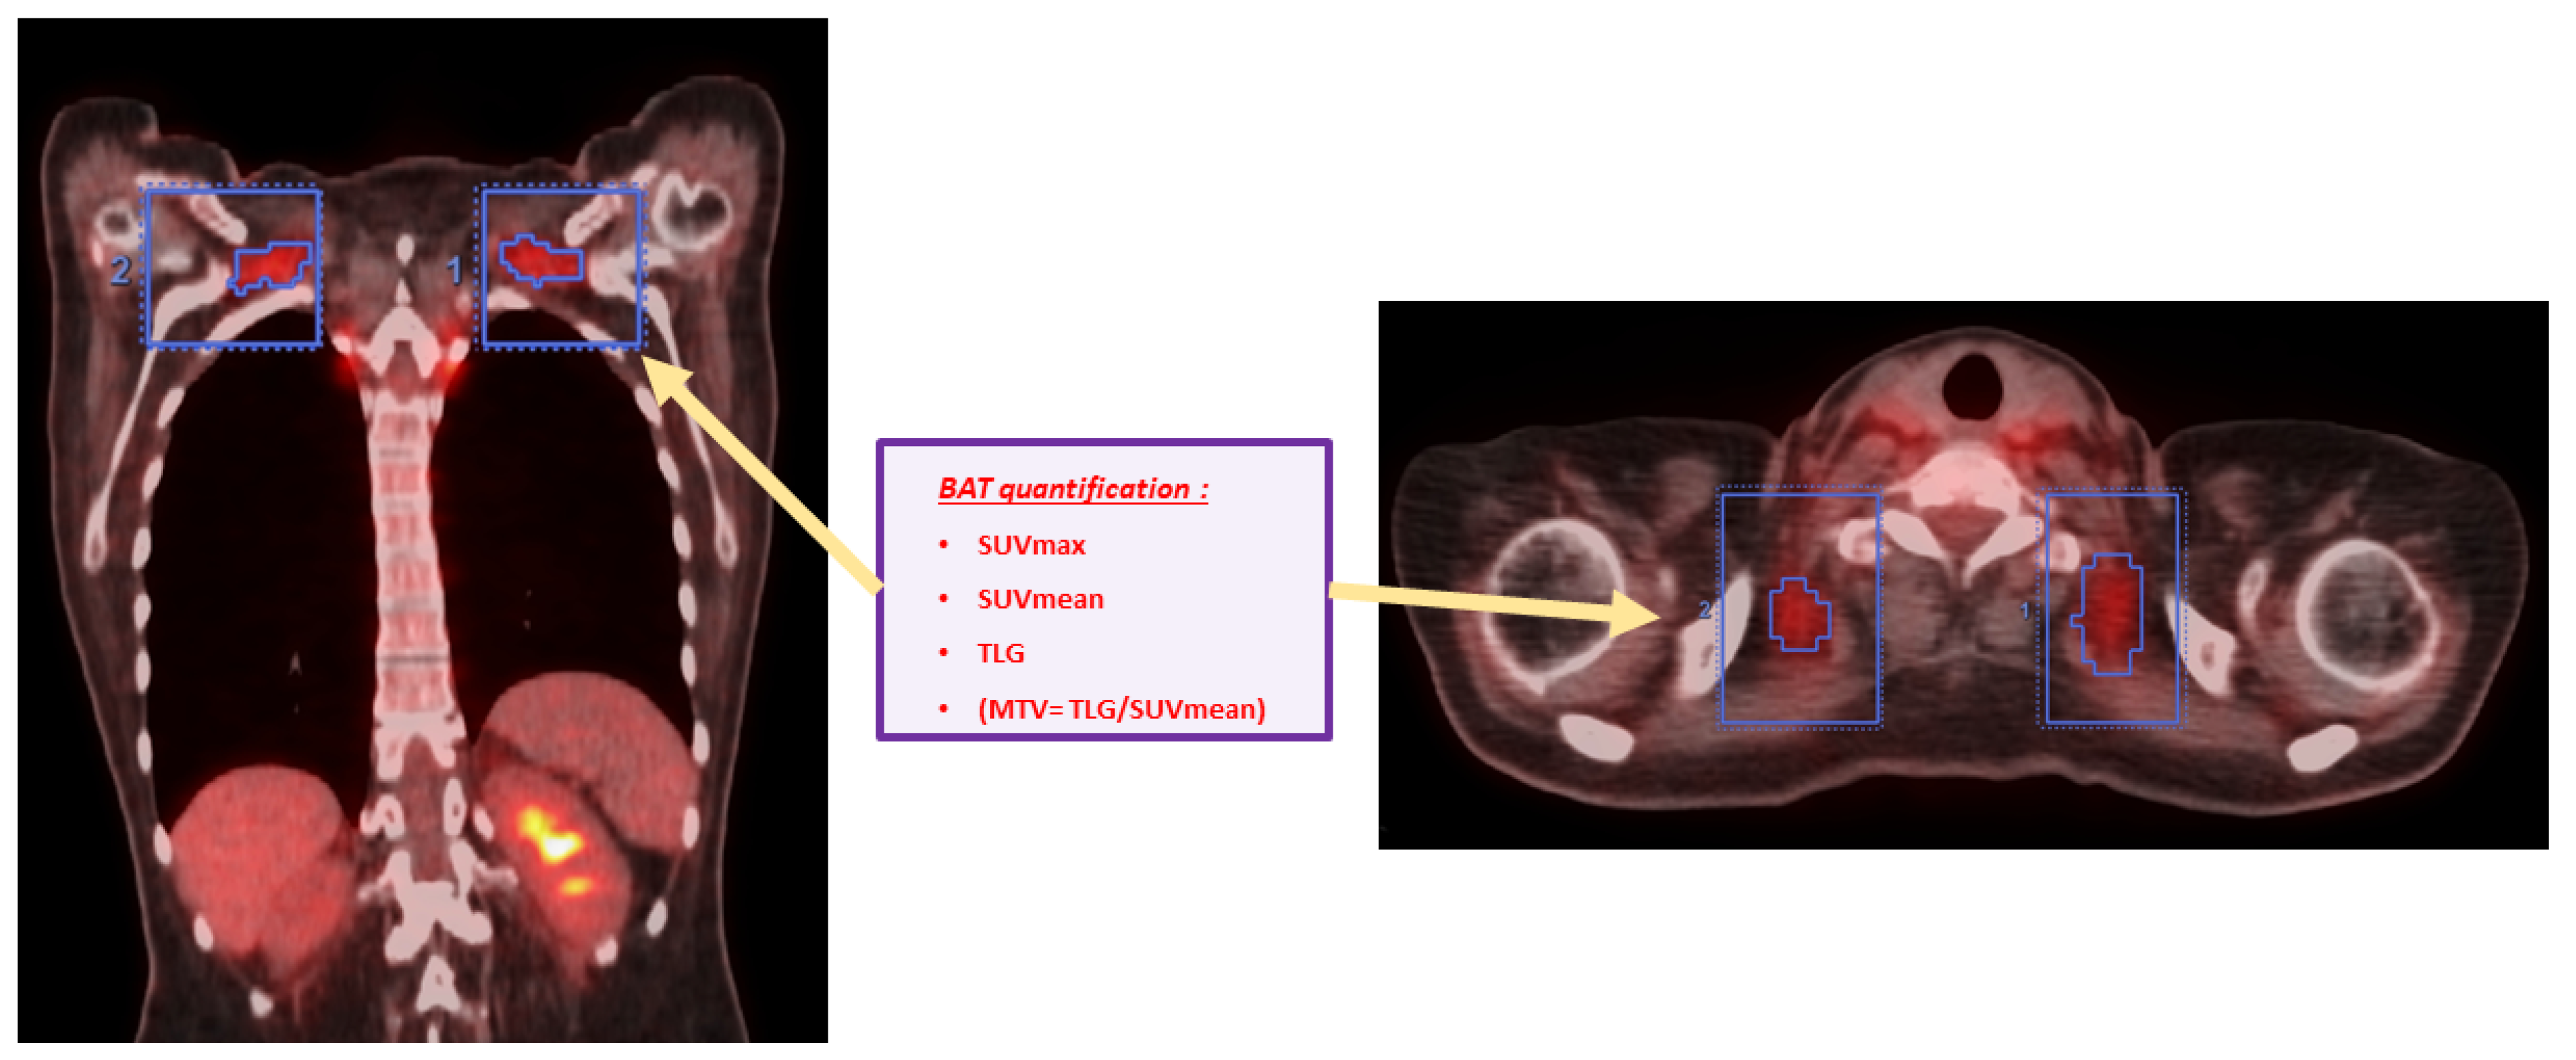

2.3.3. Quantification of BAT Activation Intensity in Every BAT+ Scan

- Total BAT SUVmax in g/mL (Tot SUVmax) = We chose the greatest value of SUVmax measured in all of the VOIs drawn from all BAT localisations;

- Total BAT SUVmean in g/mL (Tot SUVmean) = We calculated the mean of all SUVmean values measured in all of the VOIs in all BAT localisations;

- Total BAT TLG in cm3 × g/mL (Tot TLG) = We calculated the sum of all TLG values measured in all of the VOIs drawn from all BAT localisations;

- Total BAT MTV in cm3 (Tot MTV) = We calculated the sum of all MTV values measured through the ratio of Tot TLG/Tot SUVmean in all of the VOIs drawn from all BAT localisations.